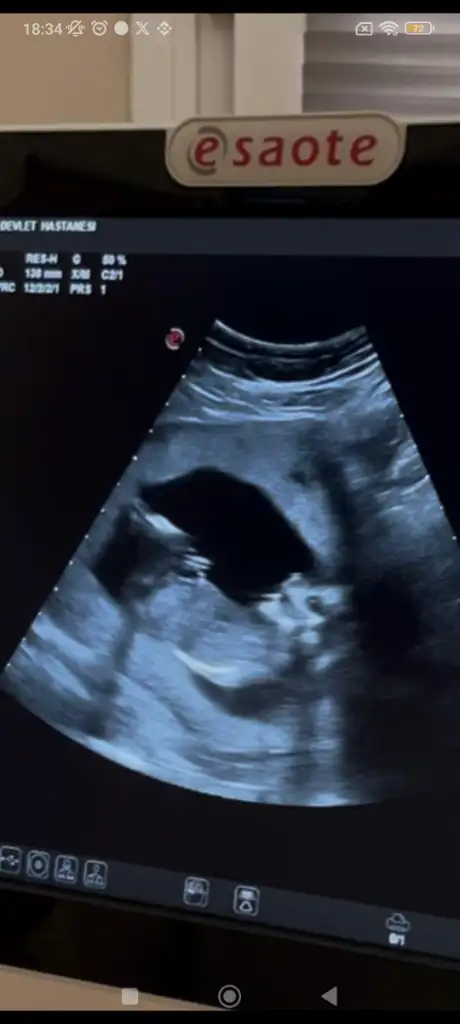

bunlarda benim torunlarım 13 haftalık ,

doktor erkek demiş , ama yanılma olurmu anlayan var mı